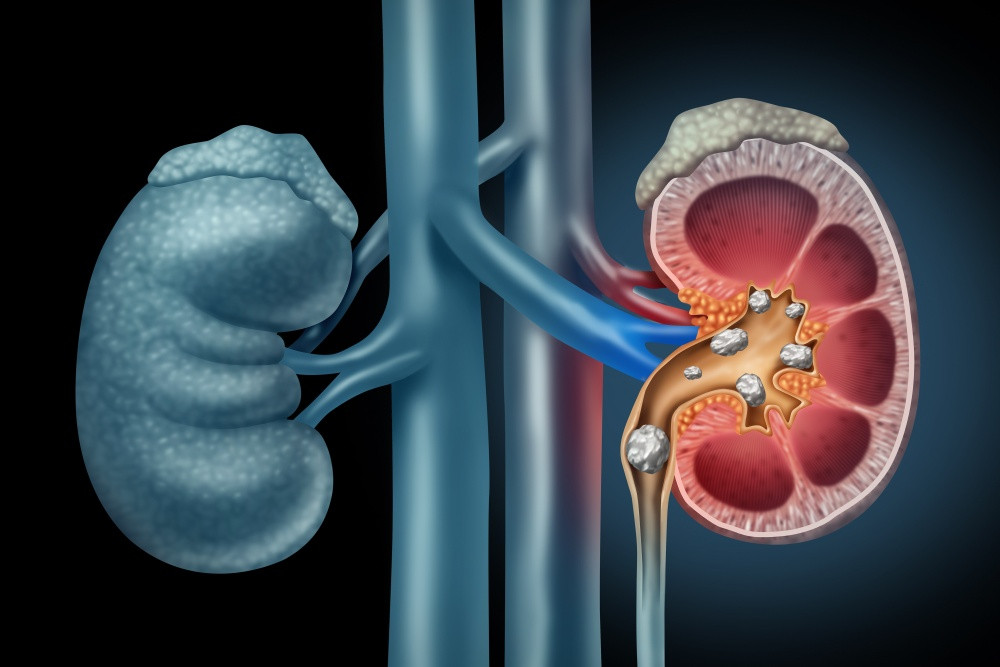

10. Darah dalam Urine

Pada kondisi normal, ginjal menyaring limbah dari darah tanpa membiarkan sel darah masuk ke urine. Namun, jika ginjal rusak, sel darah bisa bocor ke dalam urine. Darah dalam urine tidak hanya menandakan gangguan ginjal, tetapi juga bisa menjadi gejala tumor, batu ginjal, atau infeksi. Kondisi ini sebaiknya segera diperiksakan ke dokter untuk mengetahui penyebabnya.